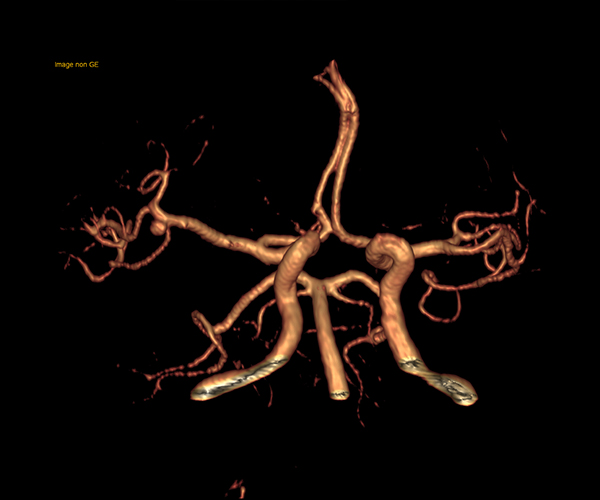

L’augmentation de l’effet de susceptibilité magnétique à plus haut champ permet d’améliorer la détection des hémorragies et est utilisé également dans l’imagerie de perfusion (tumeurs) et l’IRM fonctionnelle (BOLD). L’allongement du T1 à plus haut champ entraîne une meilleure saturation des tissus statiques et par conséquent une augmentation du contraste sang/tissus dans l’AngioIRM.